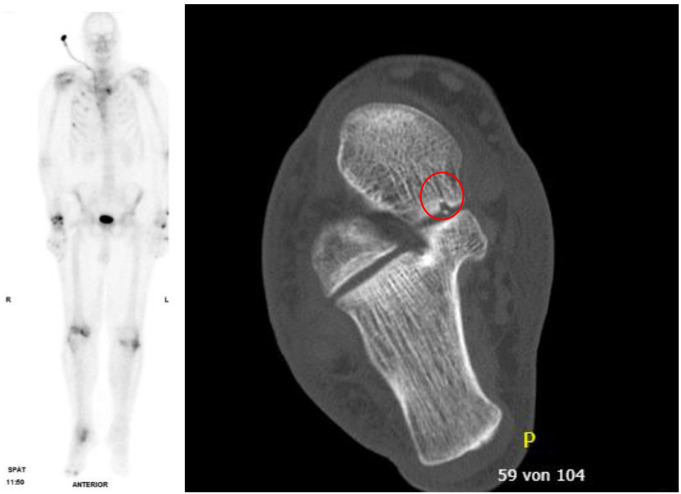

Introduction: After structured (S3 guideline, ATLS®) acute care of multiple trauma patients in trauma centers, post-acute missed injuries continue to occur with incidence rates ranging from 1.3 to 39% as described in literature. The aim of the tertiary survey was the reduction of these rates. However, high numbers of missed injuries continue to be reported. The aim of this prospective, single-center, blinded clinical diagnostic study was to determine whether the standardised use of 3-phase whole-body skeletal scintigraphy in severely injured patients can reduce the number of missed injuries compared with the established standard procedure for polytrauma diagnosis.

Methods: 26 patients aged 18 years or older (median 53.5 years, 4 female, 22 male) with an ISS ≥ 9 were evaluated by an orthopaedic and trauma surgeon using skeletal scintigraphy after completion of standardised trauma room diagnostics and tertiary survey, a median of 7 days after trauma. All clinical and diagnostic examinations were then analysed and a final consensus was reached on the bony injuries. An evaluation of each procedure against the consensus was performed for the whole body and five body regions.

Results: Skeletal scintigraphy was clearly superior to the established method (sensitivity 98.8% vs. 75.4%). Of the 60 additional bony injuries identified, 25 were treated without therapeutic consequences. Twenty-nine were treated conservatively without additional immobilisation and five with additional immobilisation. One unnecessary immobilisation was ended and no surgical treatment was required.

Conclusion: Three-phase whole-body skeletal scintigraphy is a low-risk, highly sensitive tool for reducing the incidence of missed injuries. A more liberal indication for skeletal scintigraphy should be given for injuries of increasing severity and in persons with impaired consciousness or paralysis, to avoid sequelae of missed injuries.